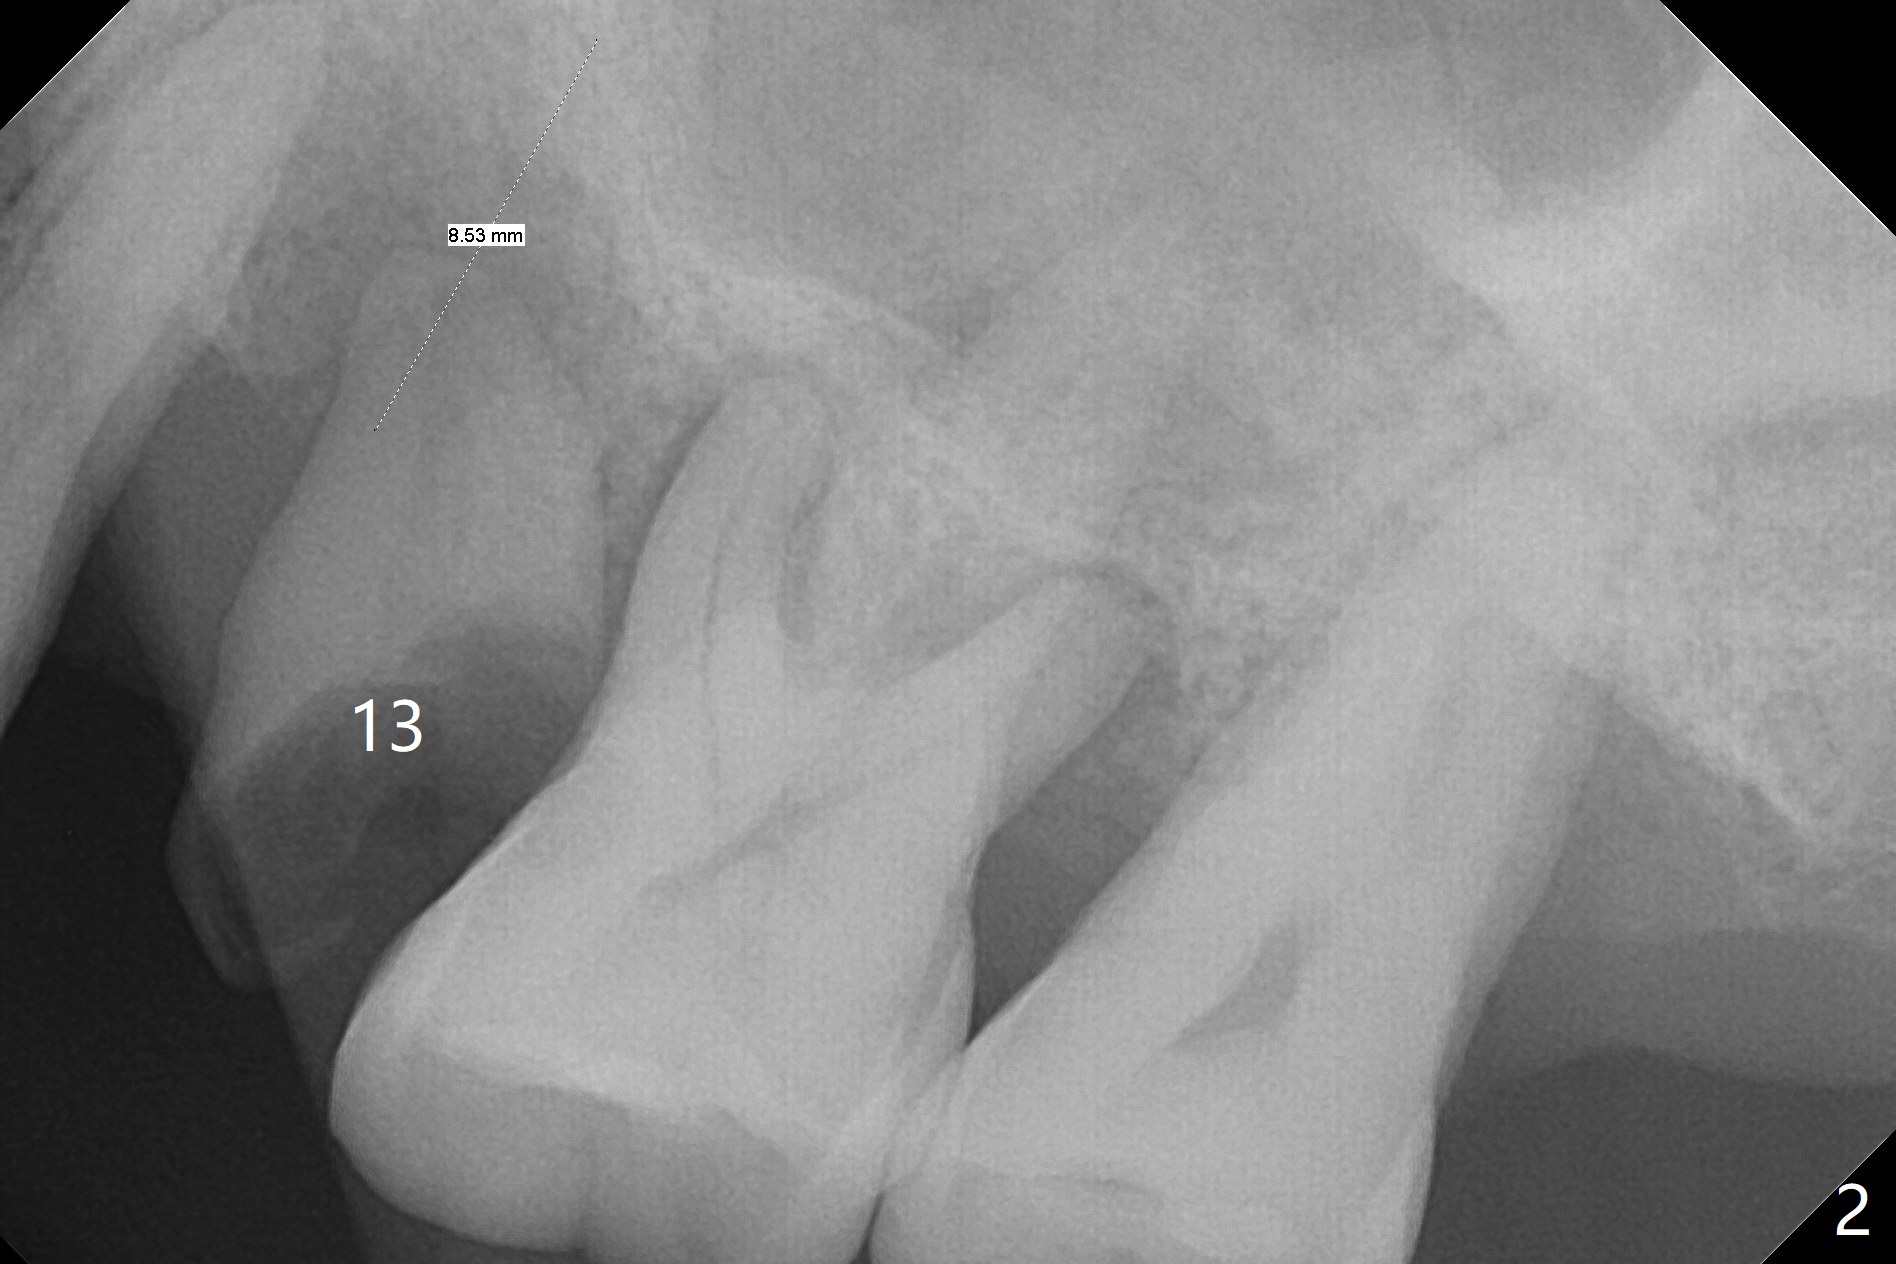

A 66-year-old man has moderate to severe chronic periodontitis. After scaling & root planing, he will return for #2 and 13 residual root removal (Fig.1,2). The latter will be done in the traditional non-sterile manner except Chlorhexidine mouth rinse and Iodine application as usual. After curettage with serrated curette, irrigation and 2x2 gauze, all of used instruments will be sent to sterilization room. A set of new instruments will be used with sterile towel spreading and sterile gloves. The strict sterile procedure is applied to sinus lift to prevent infection as this case, since the bone height is limited (Fig.2 IS). PRF and sticky bone will be carried out as well. Antibiotic Study will be terminated from now on. Take 12x9 preop CT after discussion. Prepare DIO Sinus Kit.